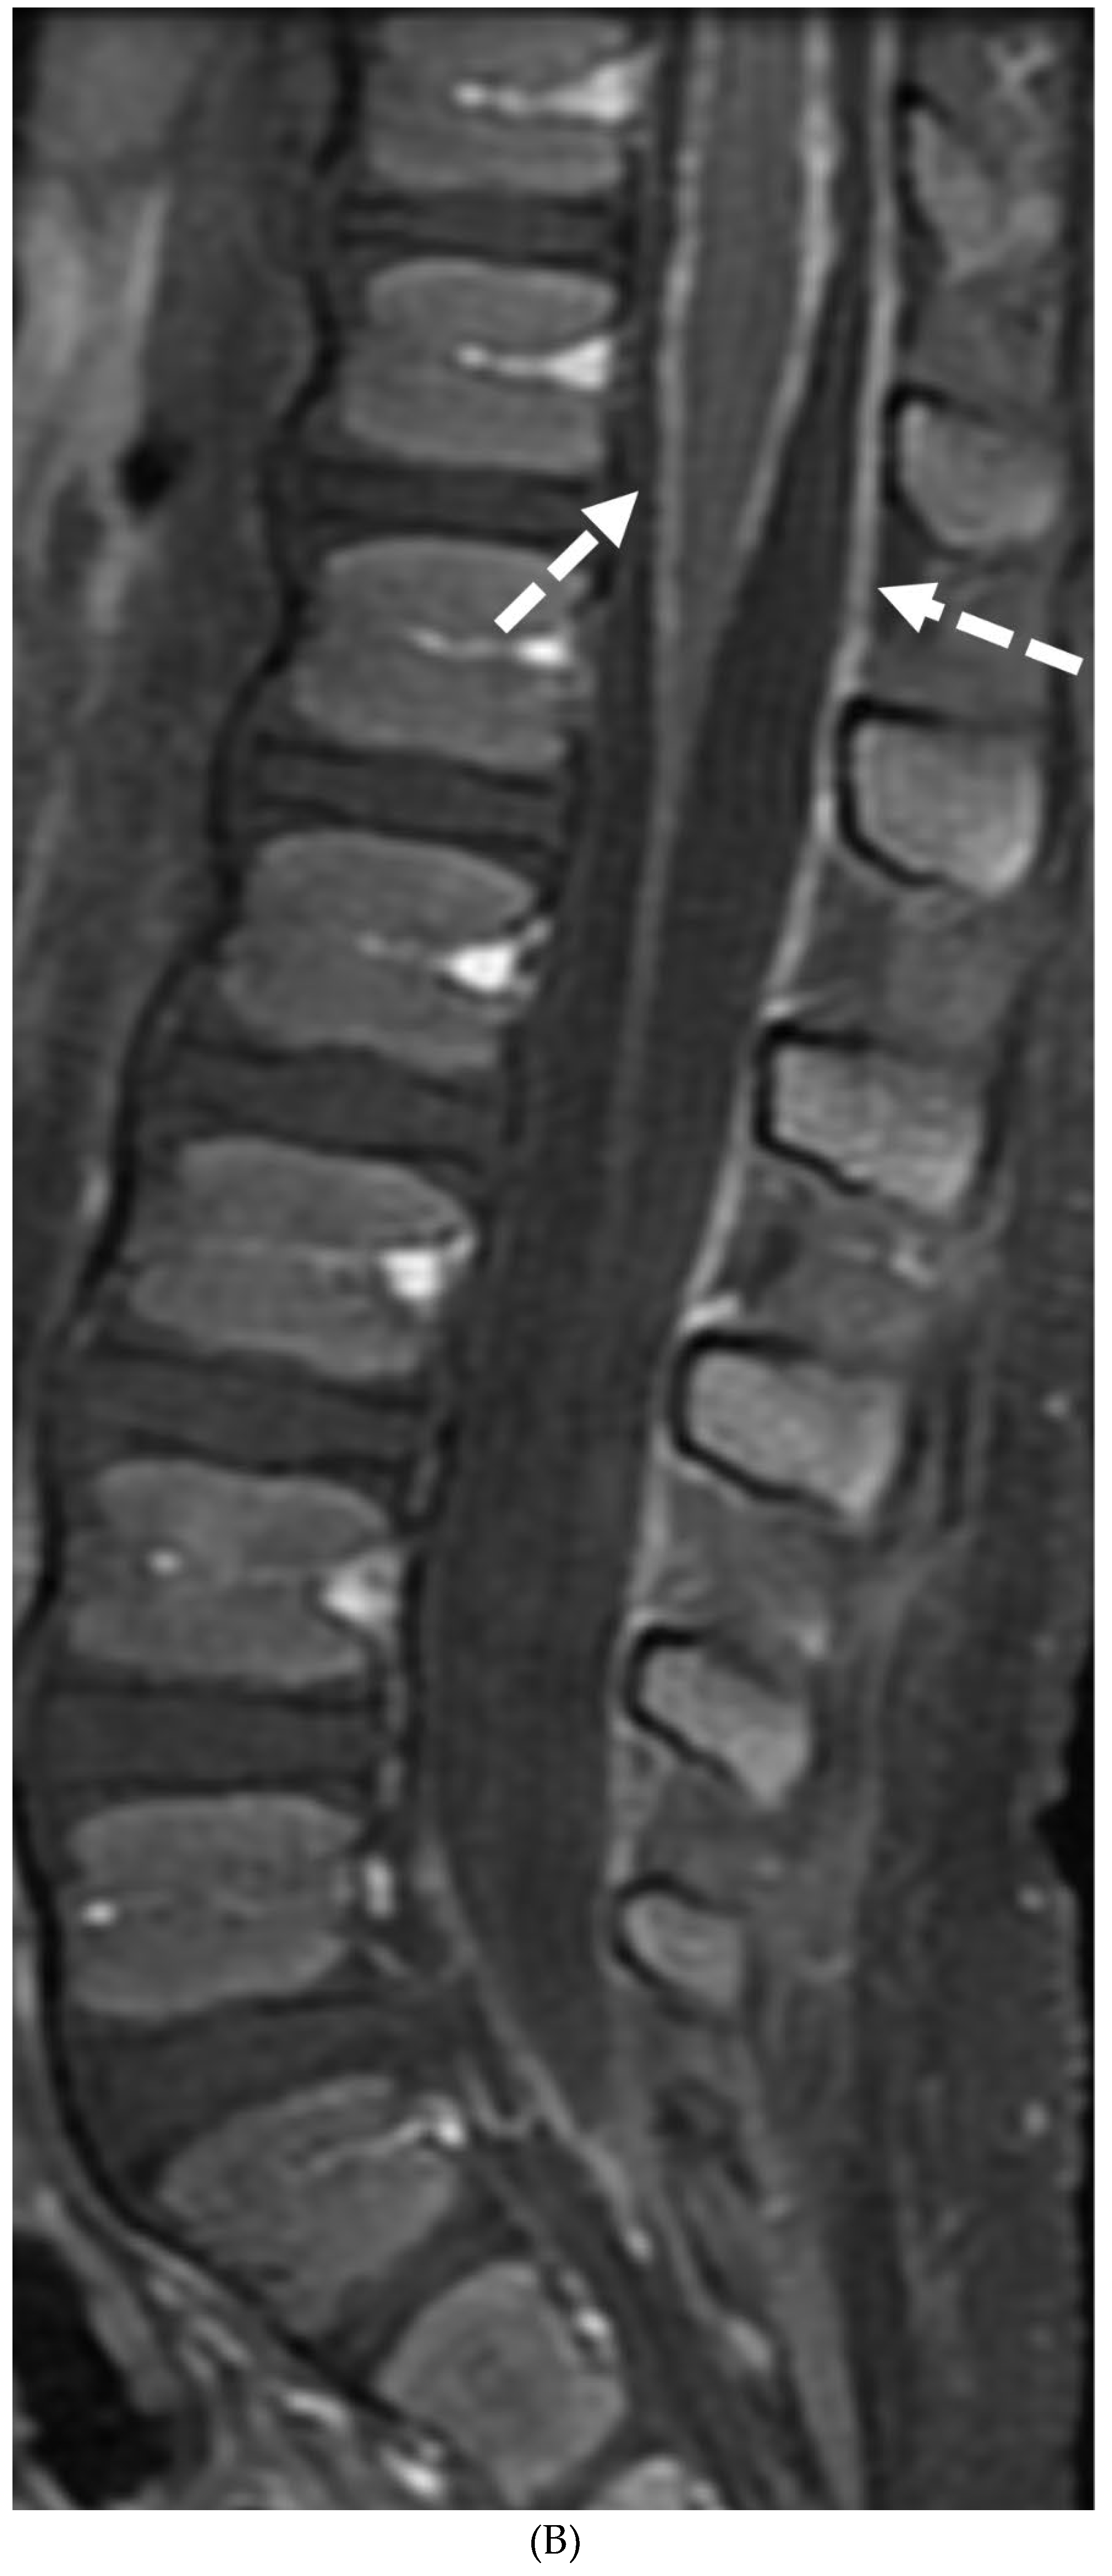

PRIMARY BRAIN TUMOR LEPTOMENINGEAL METASTASES

- Kralik SF, O'Neill DP, Kamer AP, Rodriguez E, Ho CY. Radiological diagnosis of drop metastases from paediatric brain tumours using combination of 2D and 3D MRI sequences. Clin Radiol. 2017 Oct;72(10):902.e13-902.e19. Epub 2017 May 22. PMID: 28545686. [CrossRef]

- Silva, F.A.B., Senerchia, A.A., Cappellano, A. et al. Medulloblastoma and Drop Metastasis: MRI Evaluation and Optimized Protocol. Curr Radiol Rep 3, 26 (2015). [CrossRef]

- Harrison SK, Ditchfield MR, Waters K. Correlation of MRI and CSF cytology in the diagnosis of medulloblastoma spinal metastases. Pediatr Radiol. 1998 Aug;28(8):571-4. PMID: 9716623. [CrossRef]

- Singh SK, Leeds NE, Ginsberg LE. MR imaging of leptomeningeal metastases: comparison of three sequences. AJNR Am J Neuroradiol. 2002 May;23(5):817-21. PMID: 12006284; PMCID: PMC7974747.

- Porto L, Kieslich M, Bartels M, Schwabe D, Zanella FE, Du Mesnil R. Leptomeningeal metastases in pediatrics: magnetic resonance image manifestations and correlation with cerebral spinal fluid cytology. Pediatr Int. 2010 Aug;52(4):541-6. PMID: 20534022. [CrossRef]